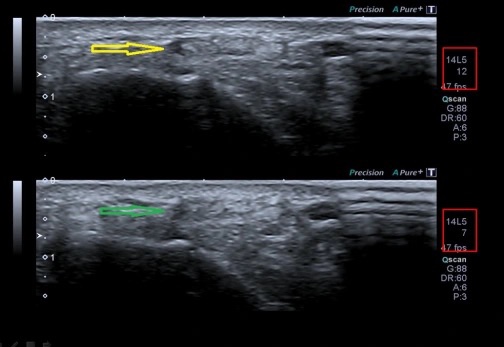

¿Pero qué logramos en realidad usando una u otra frecuencia? Debemos partir de la base que siempre debemos usar la mayor frecuencia posiblepara obtener la imagen con máxima resolución posible.

Para realizar el estudio de un músculo, por ejemplo, usaremos, dentro de las frecuencias altas, la más alta si el músculo es muy superficial, pero si el músculo es más profundo y/o el paciente es muy voluminoso quizá sea bueno bajar un salto de frecuencia, así ganaremos un poco más de visión profunda aunque perdamos un poco de resolución o nitidez.

Otro ejemplo…para hacer un hombro, usaré frecuencia alta de 12 mHz si en paciente es muy musculoso (mucha profundidad) y 18 mHz si el paciente es muy delgado (poca profundidad), o de otra manera, mi sonda lineal (alta frecuencia) puede usar varias frecuencias altas en función de las necesidades del estudio.

Si aumentamos la frecuencia tendremos menor poder de penetración pero mayor resolución.

Si disminuimos la frecuencia tendremos mayor poder de penetración pero menor resolución.